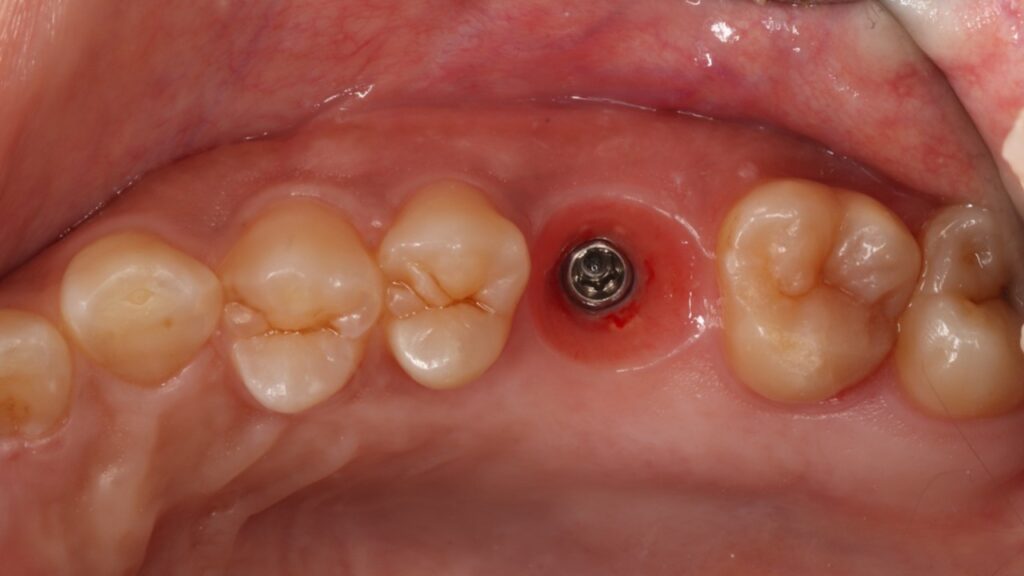

即時埋入での対応

上の奥歯は上顎洞までの距離が短くインプラントが難しいことも多いのですが、即時埋入用に開発されたインプラントを使えば抜歯と同時にインプラント埋め込みまで行うことができると判断しました。

約1時間で抜歯とインプラント埋め込みが終了しました。

条件によっては即時埋入が出来ないことも多くありますが、もし即時埋入が可能であれば術後の痛みや腫れも少なく、短期間で冠をかぶせることが出来ます。

術後も痛みや腫れはあまりなく順調に経過しました。